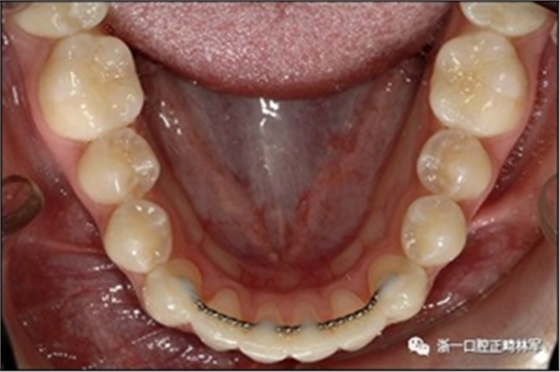

臨床檢查顯示固定保持器完好,弓絲沒(méi)有斷裂(圖13)。在下頜右側(cè)中切牙唇側(cè)和鄰近側(cè)切牙的舌側(cè)注意到有牙齦退縮。這些牙齒在退縮方向上存在顯著的扭矩差異。下頜的左側(cè)尖牙頰側(cè)錯(cuò)位,而右側(cè)尖牙舌側(cè)傾斜。三維射線照片證實(shí)了下頜右側(cè)尖牙面?zhèn)妊啦酃菃适?,右?cè)中切牙的喪失程度較輕。右側(cè)側(cè)切牙根也從舌側(cè)骨面上扭轉(zhuǎn)出來(lái)(圖14)。

圖13.粘合到尖牙和切牙上的柔性螺旋弓絲保持器,伴有牙齦退縮和附著喪失,中切牙之間嚴(yán)重的扭矩差異以及兩顆尖牙的橫向移動(dòng)和扭矩。牙周問(wèn)題和牙齒移動(dòng)的嚴(yán)重程度均為牙周正畸聯(lián)合治療的指征:A,正面視圖; B,咬合面視圖。